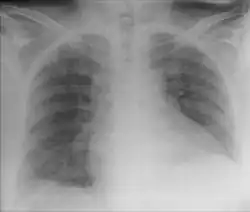

Chest X-ray of the same patient as the picture above. A small crescent of air can be seen under the right part of the diaphragm, caused by Chilaiditi's sign. However, it could easily be mistaken for free intra-abdominal air (pneumoperitoneum) which could mistakenly be attributed to bowel perforation.

Normally this causes no symptoms, and this is called Chilaiditi's sign. The sign can be permanently present, or sporadically. This anatomical variant is sometimes mistaken for the more serious condition of having air under the diaphragm (pneumoperitoneum) which is usually an indication of bowel perforation, possibly leading to surgical interventions.